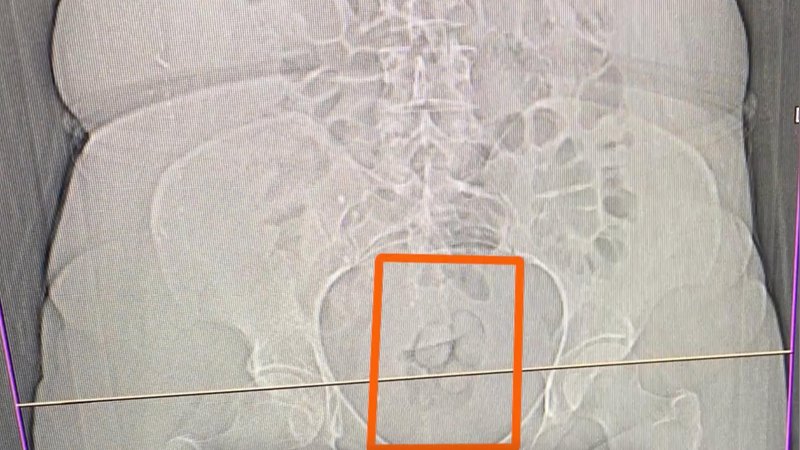

Gözaltına alınan 4 şüpheliden S.S.'nin şüpheli davranışları üzerine tomografi çekildi ve midesinde 21,39 gram metamfetamin olduğu tespit edildi. Uyuşturucu madde doğal yollarla çıkartılırken, adliyeye sevk edilen 4 şüpheli hakkında 'Uyuşturucu veya uyarıcı madde imal ve ticareti" suçundan işlem yapıldı.